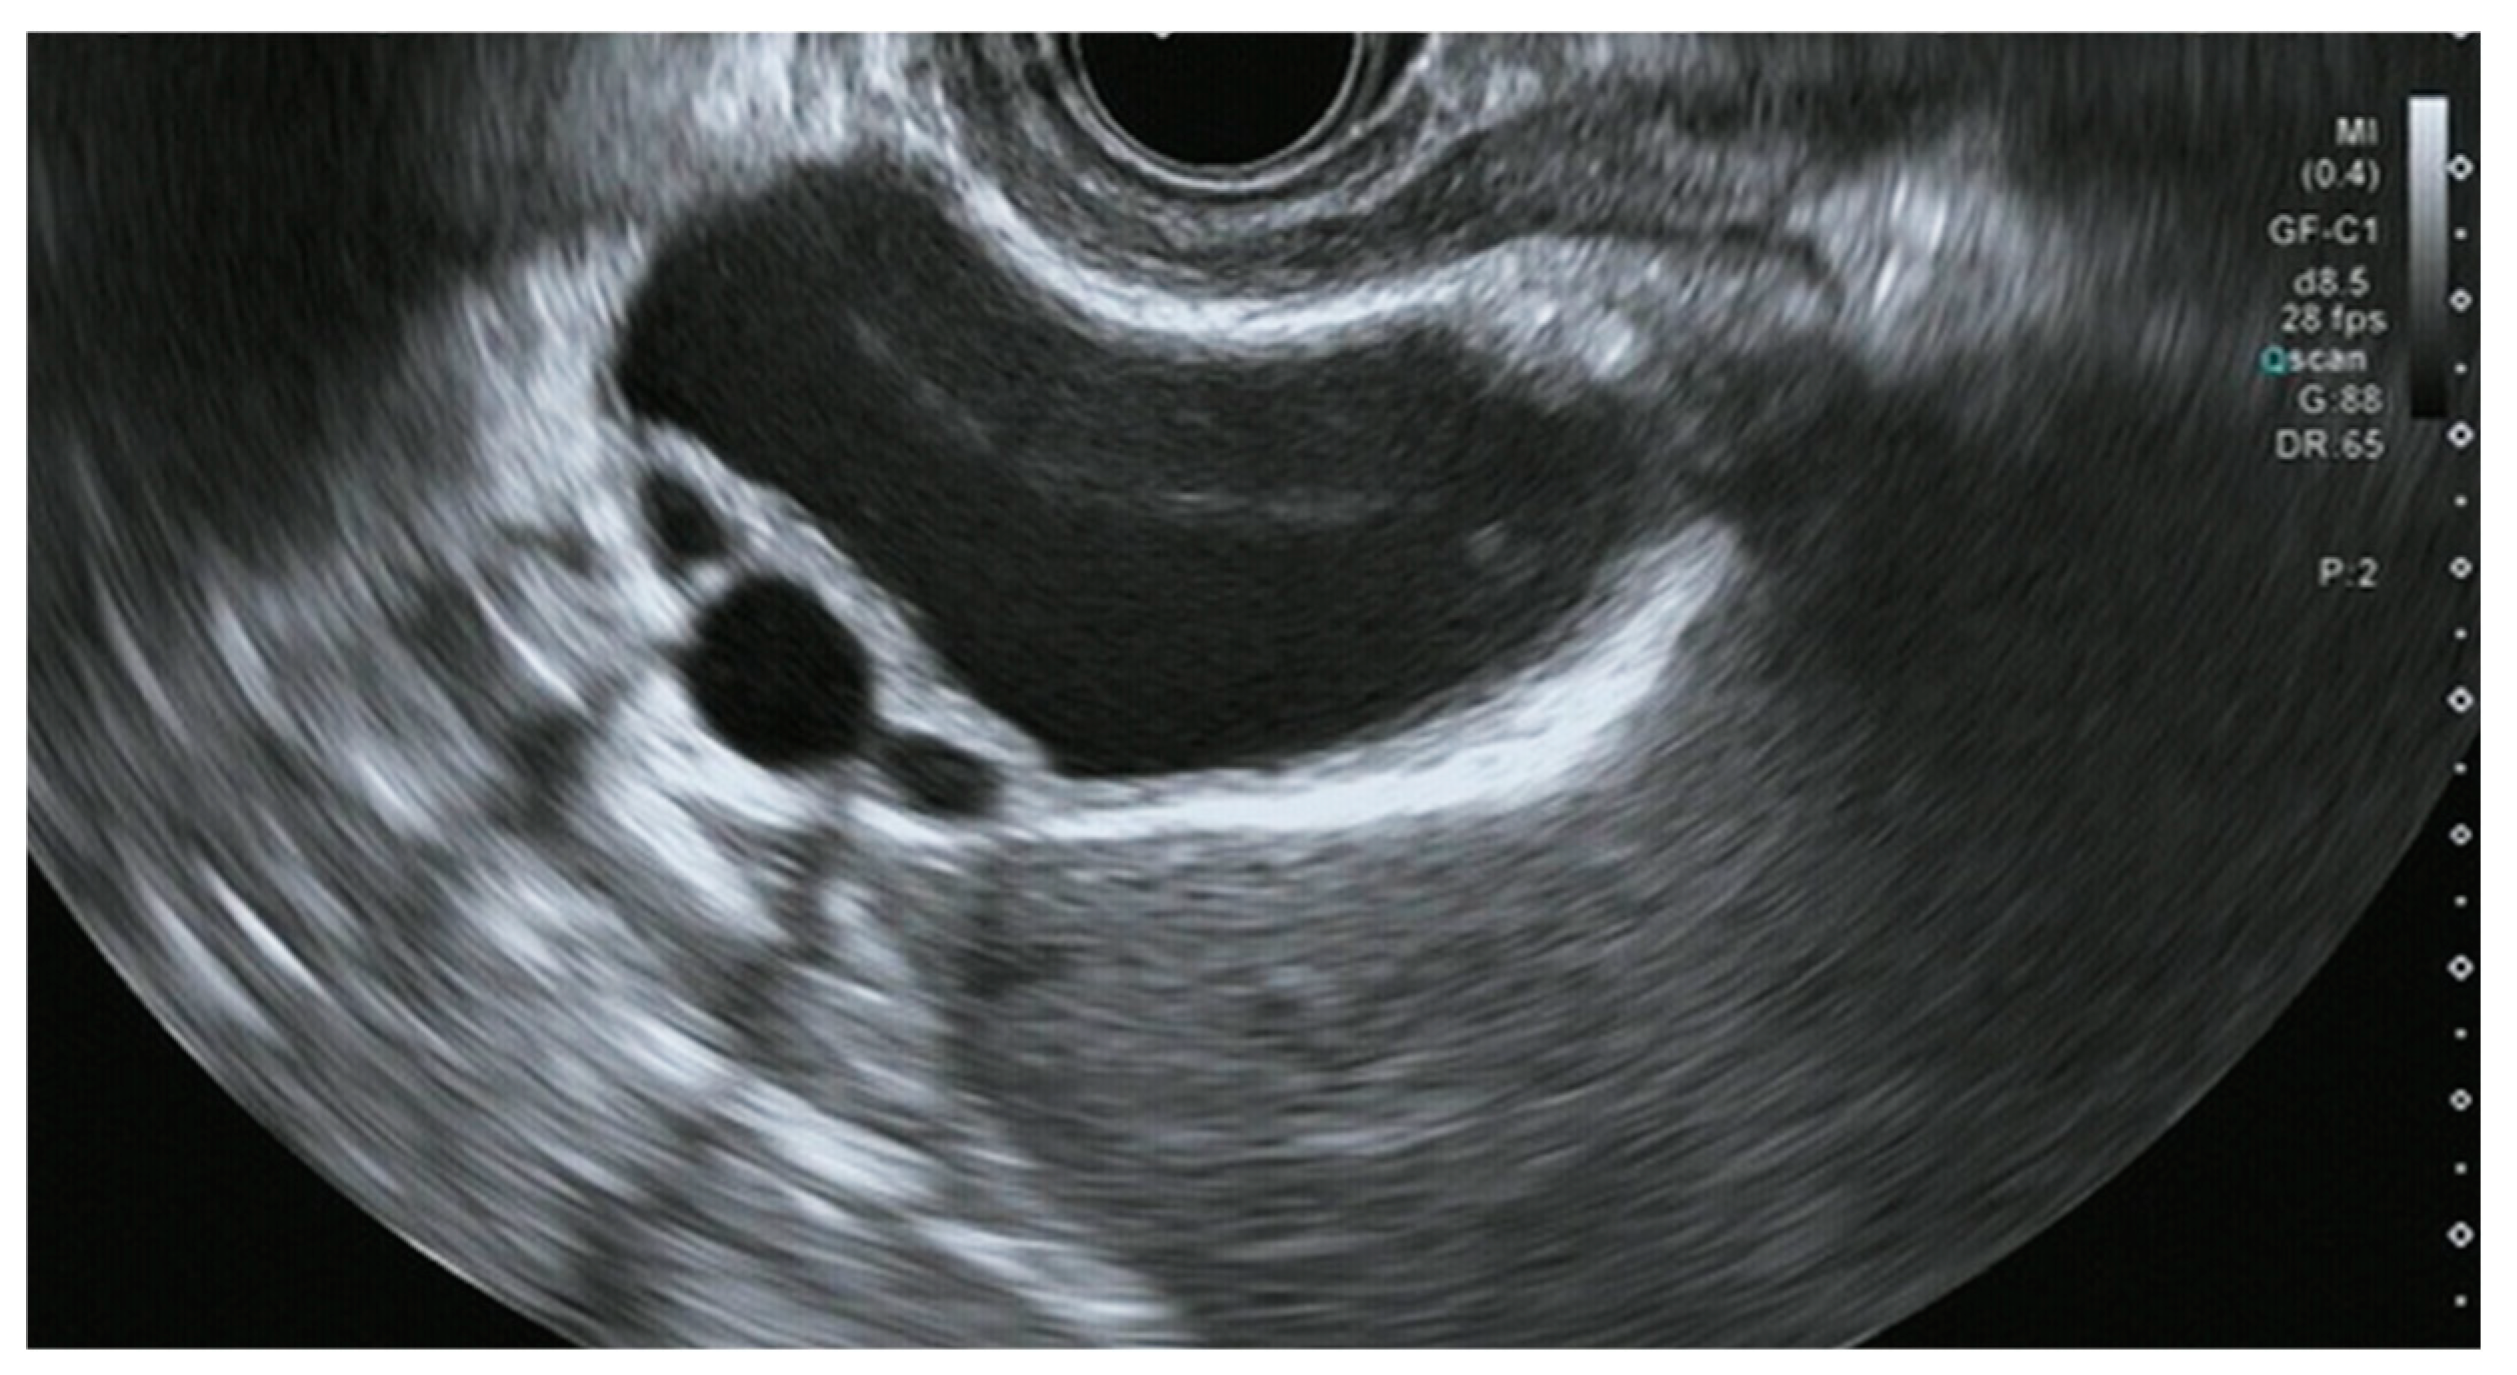

- Sugimoto, M.; Irie, H.; Takasumi, M.; Hashimoto, M.; Oka, Y.; Takagi, T.; Suzuki, R.; Konno, N.; Asama, H.; Sato, Y.; et al. A simple method for diagnosing gallbladder malignant tumors with subserosa invasion by endoscopic ultrasonography. BMC Cancer 2021, 21, 288. [Google Scholar] [CrossRef]